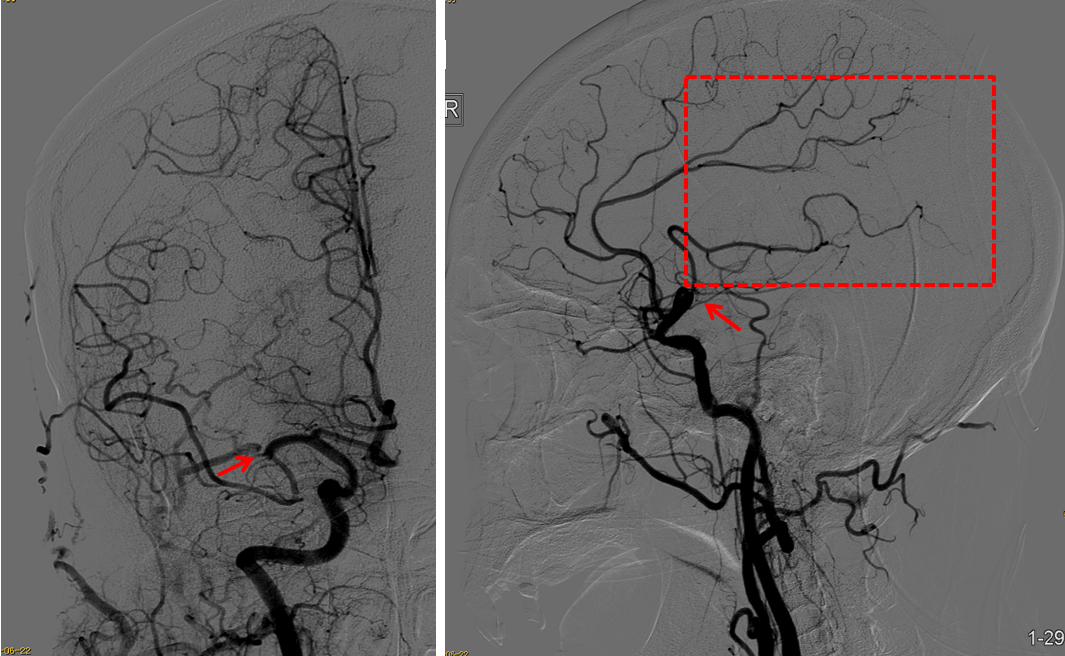

策略:支架取栓

技术:SWIM

评分:NIHSS 7分,90天mRS:2分

微导管要超选足够远,至M2段。

支架规格齐全,本病例4*30支架,支架足够长,增加血栓夹持力,提高开通率。

该病例是心源性栓塞,血栓质韧,本例选用蛟龙4*30mm更长的取栓支架,更长长度提供更大表面积接触血栓,以独特的侧边螺旋开放结构,帮助快速高效一次三级再通。一篇研究回顾性分析了2011年6月到2017年3月使用直径4mm取栓支架及球囊指引导管作为首选治疗策略治疗ICA、MCA急性闭塞的病例。该研究中,4×30mm和 4×40mm被定义为长支架,4×20mm被定义为短支架。主要的临床结局是一次性取栓血管成功再通率(mTICI 2b/3)。研究共纳入420例患者,其中221例(53%)患者使用长支架,119例(47%)使用短支架。相对于短支架,长支架组一次性取栓血管开通率(62% vs 50%;P=0.01)和最终血管开通率(mTICI2b/3,98% vs 94%;P=0.01)更高。长支架一次性取栓成功开通率高的原因,可以从以下几方面来解释:长血栓会提供更大的表面积与取栓支架接触包裹血栓,也会在取栓过程中使张力均匀分布,在血管路径扭曲或者躁动的病人中,长支架通过增加可接受的误差范围来实现精确释放。更长的支架会增加取栓装置向血栓远端延伸的移动力,同时,在支架首个与血栓接触的网孔抓捕血栓失败的情况下,可以增加血栓取出的机会。[1]因此,通桥医疗即将上市的蛟龙4*30mm取栓支架在临床上的广泛应用值得期待。